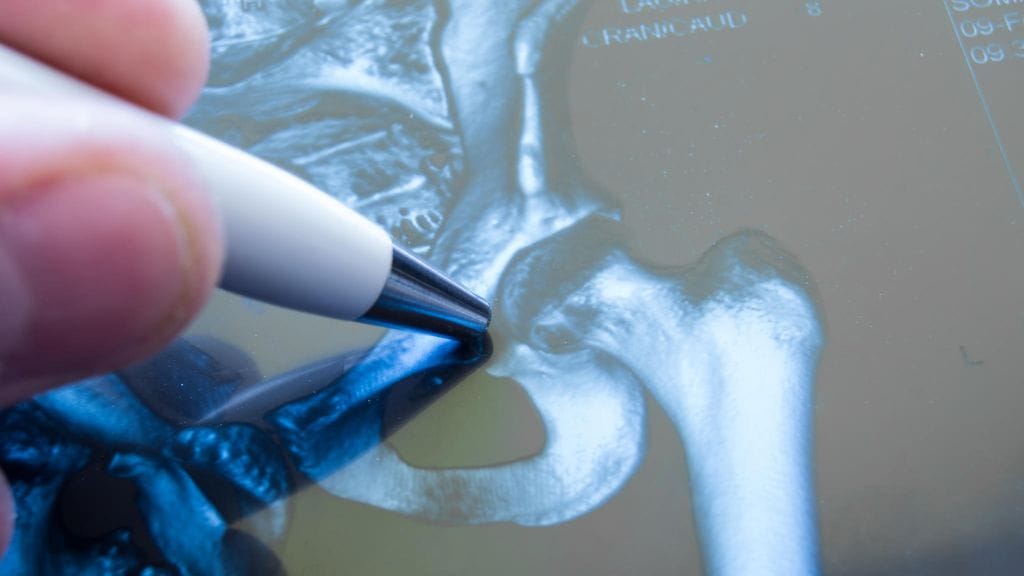

Osteoporoosia eli luukatoa sairastaa noin 400 000 suomalaista. Osteoporoosi heikentää elämänlaatua ja voi jopa johtaa kuolemaan.

Osteoporoosi on naisilla selvästi yleisempää kuin miehillä. Joka kolmas 50 vuotta täyttänyt nainen ja joka viides mies saa loppuelämänsä aikana osteoporoottisen murtuman.